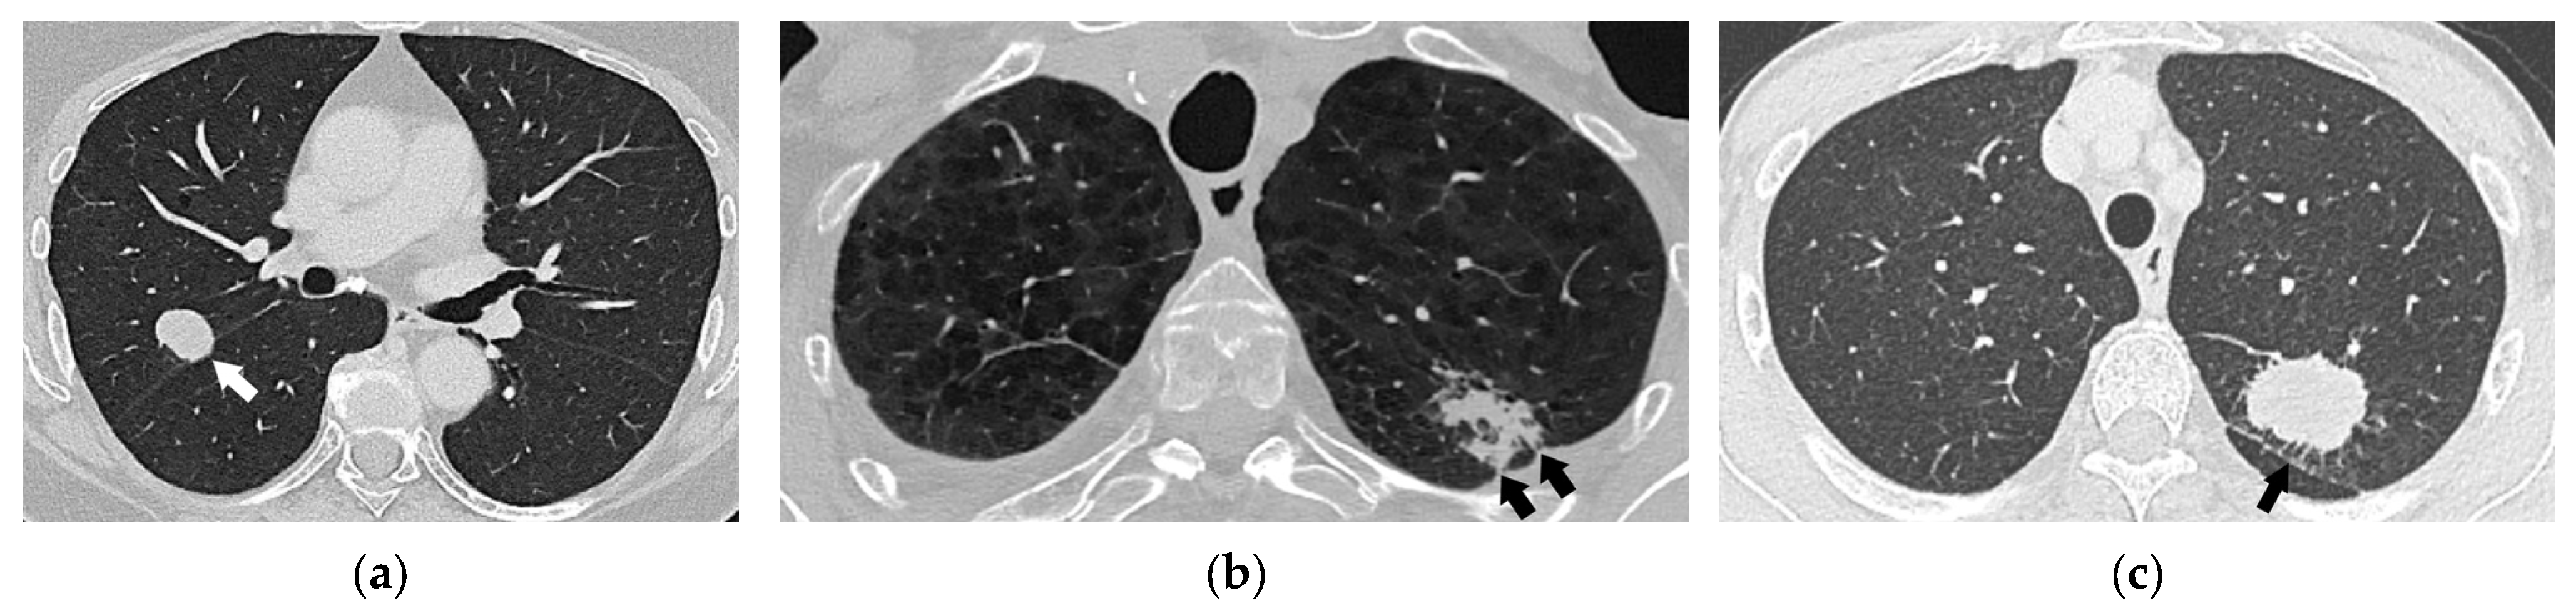

- In patients with a solid primary lung cancer with one or more separate solid tumor nodule(s) of the same histological type, separate nodules are considered to be intrapulmonary metastases (Figure 15). The presence of separate tumor nodule(s) in the same lobe as the primary tumor indicates T3 disease. If there are separate tumor nodules in a different ipsilateral lobe than that of the primary tumor, stage T4 should be determined. Lung nodules in the contralateral lung indicate distant metastases (M1a disease). Although the classification of multiple lung nodules in lung cancer patients may appear simple, it may lead to overstaging if lesions are not confirmed histologically, since the majority of lung nodules identified in patients with lung cancer are benign [37].